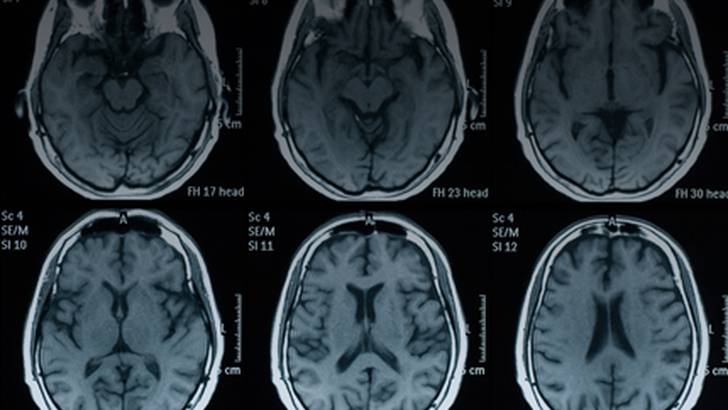

Dr. Antonio Uccelli discusses the possible near-term treatment future of patients with multiple sclerosis while at ECTRIMS 2015 in Barcelona, Spain, highlighting efforts to personalize each patient’s therapy based on MRI status and use of biomarkers as a means to select evidence-based approaches designed to maximize neuroprotection and reduce the realities of disability and brain atrophy.